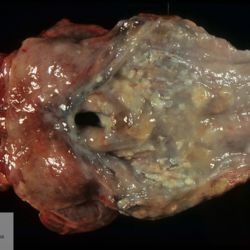

Pàgina anterior de 637 Pàgina següent 3181 total Caprine Specie: Caprine Organ: Intestine Lesion: Enteritis Lesion modifier: Enteritis - Hyperplasic (proliferative) Disease: Coccidiosis Files/Expedient: zoo11 Not viewed Avian (Exotic) Specie: Avian (Exotic) Organ: - Lesion: Aerosacculitis Lesion modifier: - Disease: - Not viewed Wildlife Specie: Wildlife Organ: Pharynx Lesion: Pharyngitis Lesion modifier: Pharyngitis - Fibrinous-necrotizing Disease: Malignant catarrhal fever Files/Expedient: zoo10 Not viewed Wildlife Specie: Wildlife Organ: Kidney Lesion: Hydroureter Lesion modifier: - Disease: Malignant catarrhal fever Files/Expedient: zoo10 Not viewed Wildlife Specie: Wildlife Organ: Skin Lesion: Dermatitis Lesion modifier: - Disease: Malignant catarrhal fever Files/Expedient: zoo10 Not viewed Pàgina anterior de 637 Pàgina següent Títol Select...Avian (Exotic) (110)Avian (Poultry) (76)Bovine (317)Canine (935)Caprine (47)Equine (257)Feline (326)Ferret (19)General (127)Marine mammal (22)Non-human primate (20)Ovine (328)Porcine (379)Rabbit (61)Reptile (38)Rodent (28)Wildlife (91) Format Select...- (60)Abomasum (37)Adrenal gland (10)Blood (7)Blood vessel (50)Body as a whole (19)Bone (57)Bone marrow (21)Brain (93)Cloaca (1)Diaphragm (2)Ear (5)Esophagus (39)Eye (16)Fetus (12)Gallbladder (23)Gizzard (2)Heart (265)Intestine (356)Joint (32)Kidney (443)Larynx (5)Liver (326)Lung (264)Lymph node (91)Mammary gland (10)Mediastinum (1)Muscle (22)Nasal cavity (22)Nerve (7)Omasum (5)Oral cavity (63)Ovary (14)Oviduct (8)Pancreas (7)Parathyroid (5)Penis (10)Peritoneum (65)Pharynx (9)Pituitary gland (6)Placenta (7)Prostate (8)Proventriculus (3)Reticulum (1)Rumen (28)Sinus (7)Skin (181)Spinal cord (15)Spleen (105)Stomach (125)Teeth (1)Testicle (11)Thoracic cavity (31)Thymus (13)Thyroid gland (5)Tongue (32)Tonsils (11)Trachea (11)Urethra (5)Urinay bladder (61)Uterus (27)Vagina (1)Vulva (1)Yolk sac (1) Cobertura Select...- (152)Abomasitis (26)Abscess (27)Acidosis (1)Adenocarcinoma (20)Adenoma (9)Aerosacculitis (6)Agenesis (1)Agnathia (1)Alopecia (7)Amyloidosis (12)Aneurysm (6)Angiectasis (1)Anthracosis (1)Arteritis (11)Arthritis (15)Arthrogryposis (6)Artifact (4)Ascites (13)Atelectasis (8)Atherosclerosis (5)Atresia (1)Atrial septal defect (2)Atrophy (10)Autolysis (7)Bronchitis (6)Bronchopneumonia (26)Cachexia (2)Carcinoma (103)Cardiomyopathy (19)Cellulitis (2)Chemodectoma (4)Cholangiohepatitis (4)Cholangitis (19)Cholecystitis (4)Cholestasis (5)Chondrodysplasia (2)Chondrosarcoma (2)Chronic passive congestion (13)Chylothorax (2)Cirrhosis (6)Coelomitis (3)Coenurus cerebralis (4)Colitis (40)Congestion (17)Conjunctivitis (5)Coronitis (3)Cryptorchidism (3)Cyst (25)Cystitis (24)Dermatitis (69)Diaphragmatic hernia (4)Dilation (28)Discospondylitis (1)Disseminated intravascular coagulation (7)Dyschondroplasia (1)Dysplasia (29)Ectopia cordis (1)Ectopic ureter (1)Edema (55)Emphysema (5)Encephalitis (5)Endocardiosis (14)Endocarditis (26)Endometritis (5)Enteritis (118)Enterolith (6)Epulis (3)Esophagitis (14)Fasciitis (1)Fibrosis (7)Fibrous osteodystrophy (8)Fistula (1)Folliculitis (3)Fracture (2)Gastritis (34)Gingivitis (5)Glioma (8)Glomerulonephritis (21)Glossitis (25)Glycogenosis (1)Gout (8)Granuloma (2)Granulosa cell tumor (4)Hemangioma (9)Hemangiosarcoma (46)Hematoma (8)Hemoglobinuria (2)Hemopericardium (12)Hemoperitoneum (2)Hemorrhage (100)Hemosiderosis (7)Hemothorax (2)Hepatitis (78)Hernia (11)Histiocytosis (3)Hydatid cyst (11)Hydrocephalus (9)Hydrometra (1)Hydronephrosis (22)Hydropericardium (6)Hydrothorax (3)Hydroureter (5)Hyperkeratosis (8)Hyperostosis (4)Hyperplasia (37)Hypertrophy (9)Hypopigmentation (1)Hypoplasia (7)Hypopyon (1)Impaction (6)Infarction (63)Insulinoma (6)Intussusception (5)Jaundice (17)Laminitis (2)Laryngitis (2)Leiomyoma (5)Leukemia (13)Lipidosis (36)Lipoma (7)Lymphadenitis (45)Lymphadenopathy (7)Lymphangiectasia (6)Lymphangitis (5)Lymphoma (221)Malacia (11)Malignant melanoma (15)Mast cell tumor (11)Mastitis (8)Megaesophagus (2)Melanosis (3)Melena (4)Meningioma (6)Meningitis (6)Meningocele (2)Meningoencephalitis (5)Mesothelioma (5)Methemoglobinemia (2)Mineralization (10)Mucocele (5)Mucometra (1)Multilobular bone tumor (1)Mummification (3)Myelofibrosis (1)Myocarditis (4)Myositis (5)Necrosis (81)Nephritis (113)Nephroblastoma (6)Nephrosclerosis (1)Nephrosis (14)Neuritis (1)Obstruction (13)Omasitis (4)Omphalitis (1)Omphalophlebitis (7)Orchitis (4)Osteoarthrosis (5)Osteomyelitis (9)Otitis (2)Palatoschisis (3)Pancreatitis (3)Panniculitis (3)Papilloma (7)Parakeratosis (14)Patent ductus arteriosus (6)Peliosis hepatis (1)Perforation (17)Pericarditis (35)Peritonitis (39)Persistent right aortic arch (1)Pharyngitis (2)Pheochromocytoma (2)Phlebitis (2)Placentitis (6)Pleuritis (21)Pleuropneumonia (24)Pneumonia (109)Pneumothorax (3)Polycystosis (14)Polyp (5)Polyserositis (6)Posthitis (1)Proctitis (4)Prolapse (3)Prostatitis (3)Proventriculitis (1)Pyelonephritis (24)Pyometra (6)Pyothorax (4)Rhinitis (11)Rumenitis (6)Rupture (24)Salpingitis (3)Sarcoma (57)Sclerosis (1)Scoliosis (2)Seminoma (2)Sequestrum (2)Serous atrophy (14)Sinusitis (7)Splenitis (14)Splenomegaly (9)Spondylitis (6)Spondylosis (1)Stenosis (9)Stomatitis (32)Tenosynovitis (2)Teratoma (3)Thricobezoar (2)Thrombosis (16)Tonsilitis (4)Torsion (13)Tracheitis (4)Tympany (7)Typhlitis (8)Typhlocolitis (4)Ulcer (43)Urethritis (1)Urolithiasis (36)Uroperitoneum (1)Uveitis (1)Vasculitis (15)Ventricular septal defect (3)Volvulus (11) Matèria Select... - (14)- (1653)- (152)Abomasitis - Catarrhal (2)Abomasitis - Catarrhal-hemorrhagic (1)Abomasitis - Chronic (1)Abomasitis - Fibrinous-necrotizing (2)Abomasitis - Hyperplasic (5)Abomasitis - Hyperplasic - Chronic (1)Abomasitis - Necrotic (1)Abomasitis - Necrotizing (2)Abomasitis - Ulcerative (5)Adenocarcinoma (9)Aerosacculitis - Granulomatous (1)Amyloidosis - Chronic (1)Arteritis - Necrotic (2)Arteritis - Necrotizing (1)Arthritis - Chronic (4)Arthritis - Fibrinous-purulent (3)Arthritis - Serous (4)Arthritis - Subacute (1)Ascites - Serous (1)Atrophy - Serous (1)Bronchitis - Catarrhal (3)Bronchitis - Suppurative (1)Bronchopneumonia - Catarrhal-purulent (17)Bronchopneumonia - Fibrinous (1)Bronchopneumonia - Granulomatous (1)Bronchopneumonia - Purulent (1)Bronchopneumonia - Suppurative (5)Carcinoma - Adenocarcinoma (33)Carcinoma - Adenocarcinoma - Hepatocellular (2)Carcinoma - Adenocarcinoma - Mucinous (1)Carcinoma - Basosquamous (1)Carcinoma - Cholangiocellular (3)Carcinoma - Hepatocellular (4)Carcinoma - Metastatic (3)Carcinoma - Squamous cell carcinoma (13)Carcinoma - Transitional cell (2)Cardiomyopathy - Dilated (13)Cardiomyopathy - Hypertrophic (6)Cellulitis - Necrotizing (1)Cholangitis - Chronic (8)Cholangitis - Hyperplasic (3)Cholecystitis - Fibrinous-necrotizing (1)Coelomitis - Fibrinous (1)Coelomitis - Granulomatous (1)Colitis - Catarrhal (3)Colitis - Catarrhal-hemorrhagic (1)Colitis - Fibrinous (1)Colitis - Fibrinous-necrotizing (1)Colitis - Fibrinous-necrotizing (Diphtheritic) (6)Colitis - Granulomatous (2)Colitis - Hemorrhagic (4)Colitis - Hemorrhagic-necrotizing (3)Colitis - Necrotizing (2)Colitis - Ulcerative (6)Congestion - Chronic (2)Conjunctivitis - Hyperplasic (1)Conjunctivitis - Purulent (3)Coronitis - Ulcerative (1)Cystitis - Chronic (3)Cystitis - Fibrinous (1)Cystitis - Fibrinous-necrotizing (1)Cystitis - Follicular (1)Cystitis - Hemorrhagic (6)Cystitis - Hemorrhagic-ulcerative (1)Cystitis - Necrotizing (9)Cystitis - Perforated (1)Dermatitis - Granulomatous (14)Dermatitis - Hyperkeratotic (10)Dermatitis - Hyperplasic (proliferative) (1)Dermatitis - Hyperplastic (10)Dermatitis - Necrotizing (4)Dermatitis - Pustular (4)Dermatitis - Ulcerative (2)Dilation - Chronic (1)Discospondylitis - Necrotizing (1)Dysplasia - Follicular (5)Edema - Interstitial (6)Emphysema - Interstitial (1)Encephalitis - Granulomatous (1)Encephalitis - Nonsuppurative (1)Endocardiosis - Mitral (7)Endocardiosis - Mitral - Chronic (5)Endocarditis - Valvular (6)Endocarditis - Valvular - Mitral (7)Endocarditis - Valvular - Pulmonic (1)Endocarditis - Valvular - Subacute (1)Endocarditis - Valvular - Subaortic (5)Endocarditis - Valvular - Tricuspid (4)Endometritis - Purulent (3)Endometritis - Purulent-hemorrhagic (2)Enteritis - Catarrhal (23)Enteritis - Catarrhal - Acute (1)Enteritis - Catarrhal-hemorrhagic (5)Enteritis - Catarrhal-hemorrhagic - Acute (2)Enteritis - Fibrinous (16)Enteritis - Fibrinous - Acute (3)Enteritis - Fibrinous-necrotizing (7)Enteritis - Granulomatous (14)Enteritis - Granulomatous - Chronic (1)Enteritis - Granulomatous - Multifocal (1)Enteritis - Hemorrhagic (17)Enteritis - Hemorrhagic - Acute (1)Enteritis - Hemorrhagic-necrotizing (1)Enteritis - Hyperplasic (proliferative) (4)Enteritis - Necrotizing (4)Enteritis - Necrotizing - Acute (1)Enteritis - Necrotizing - Hemorrhagic (1)Enteritis - Necrotizing-ulcerative (2)Enteritis - Ulcerative (1)Enteritis - Ulcerative-hemorrhagic (1)Esophagitis - Erosive-ulcerative (6)Esophagitis - Necrotizing (4)Esophagitis - Ulcerative (1)Esophagitis - Ulcerative-necrotizing (1)Fasciitis - Fibrinous-purulent (1)Folliculitis - Purulent (2)Gastritis - Catarrhal (2)Gastritis - Chronic (1)Gastritis - Follicular (1)Gastritis - Hemorrhagic (2)Gastritis - Hemorrhagic-necrotizing (1)Gastritis - Hypertrophic (2)Gastritis - Inclusion bodies (1)Gastritis - Mineralization (1)Gastritis - Mycotic (1)Gastritis - Necrotizing (2)Gastritis - Ulcerative (6)Gastritis - Uremic (3)Gingivitis - Erosive (2)Gingivitis - Hyperplasic (proliferative) (1)Gingivitis - Necrotizing (1)Glomerulonephritis - Chronic (7)Glomerulonephritis - Membranoproliferative (3)Glomerulonephritis - Membranoproliferative - Chronic (1)Glomerulonephritis - Membranous (3)Glomerulonephritis - Membranous - Chronic (1)Glomerulonephritis - Proliferative (2)Glomerulonephritis - Subacute (1)Glossitis - Erosive (2)Glossitis - Granulomatous (6)Glossitis - Hyperplasic (1)Glossitis - Hyperplasic (proliferative) (2)Glossitis - Hyperplastic (1)Glossitis - Necrotizing (2)Glossitis - Necrotizing - Focal (1)Glossitis - Ulcerative (6)Glossitis - Ulcerative - Multifocal (1)Glossitis - Ulcerative - Subacute (1)Glycogenosis (1)Granuloma - Eosinophilic (1)Hemangiosarcoma - Metastatic (2)Hemorrhage - Acute (1)Hemorrhage - Subcapsular (3)Hepatitis - Abscess (9)Hepatitis - Acute (3)Hepatitis - Chronic (4)Hepatitis - Chronic interstitial (6)Hepatitis - Granulomatous (7)Hepatitis - Interstitial - Multifocal (1)Hepatitis - Interstitial - Subacute (1)Hepatitis - Necrotizing (17)Hepatitis - Necrotizing - Acute (2)Hepatitis - Necrotizing - Hemorrhagic (1)Hepatitis - Necrotizing - Subacute (1)Hepatitis - Pyogranulomatous (7)Hepatitis - Subacute (4)Hydronephrosis - Chronic (1)Hydropericardium - Chronic (1)Hyperplasia - Erythroid (1)Hyperplasia - Lymphoid (3)Hyperplasia - Myeloid (1)Hyperplasia - Nodular (8)Hypertrophy - Concentric (2)Hypertrophy - Eccentric (3)Infarction - Acute (17)Infarction - Acute - Multifocal (2)Infarction - Chronic (5)Infarction - Chronic - Multifocal (1)Infarction - Subacute (18)Infarction - Subacute - Focal (2)Laminitis - Chronic (2)Laryngitis - Necrotic (1)Laryngitis - Necrotizing (1)Leukemia - Lymphoid leukemia (2)Leukemia - Non-lymphoid leukemia (6)Lipidosis - Multifocal (1)Lipidosis - Panlobular (1)Lipidosis - Panlobular - Generalized (2)Lymphadenitis - Granulomatous (24)Lymphadenitis - Granulomatous - Chronic (3)Lymphadenitis - Hemorrhagic (1)Lymphadenitis - Necrotizing (5)Lymphadenitis - Necrotizing (caseous) (11)Lymphangitis - Granulomatous (1)Lymphangitis - Purulent (1)Lymphangitis - Ulcerative (1)Lymphoma - Alimentary lymphoma (7)Lymphoma - Cutaneous lymphoma (6)Lymphoma - Lymphosarcoma (2)Lymphoma - Mediastinal lymphoma (1)Lymphoma - Multicentric lymphoma (29)Malignant melanoma - Malignant (1)Malignant melanoma - Metastatic (1)Mast cell tumor - Metastatic (1)Mastitis - Fibrinous-purulent (2)Mastitis - Necrotic (1)Mastitis - Purulent (3)Mastitis - Suppurative (1)Meningitis - Fibrinous-purulent (2)Meningitis - Purulent (4)Meningoencephalitis - Necrotizing (3)Meningoencephalitis - Nonsuppurative (2)Mineralization - Metastatic (4)Myocarditis - Fibrous - Chronic (1)Myocarditis - Granulomatous (1)Myositis - Purulent (2)Necrosis - Acute (1)Necrosis - Cortical (5)Necrosis - Follicular (1)Necrosis - Papillary (8)Necrosis - Papillary - Acute (3)Necrosis - Subacute (3)Necrosis - Tubular (6)Nephritis - Embolic (2)Nephritis - Embolic suppurative (7)Nephritis - Granulomatous (27)Nephritis - Granulomatous - Chronic (1)Nephritis - Granulomatous - Multifocal (1)Nephritis - Interstitial (6)Nephritis - Interstitial - Acute (4)Nephritis - Interstitial - Chronic (41)Nephritis - Interstitial - Subacute (12)Nephritis - Purulent (7)Nephritis - Purulent - Acute (2)Nephritis - Purulent - Multifocal (3)Nephrosis - Cholemic (3)Nephrosis - Hemoglobinuric (10)Omasitis - Fibrinous-necrotizing (1)Omasitis - Hyperkeratotic (1)Omasitis - Necrotizing (2)Omphalophlebitis - Fibrinous-purulent (2)Omphalophlebitis - Purulent (3)Orchitis - Necrotizing (1)Osteomyelitis - Necrotizing (7)Osteomyelitis - Purulent (2)Otitis - Necrotizing (1)Otitis - Proliferative (1)Pancreatitis - Acute (1)Pancreatitis - Chronic (1)Pancreatitis - Granulomatous (1)Panniculitis - Fibrinous-purulent (1)Panniculitis - Necrotic (1)Panniculitis - Parasitic (1)Perforation - Acute (2)Pericarditis - Fibrinous (19)Pericarditis - Fibrinous - Subacute (1)Pericarditis - Fibrinous-necrotizing (1)Pericarditis - Fibrinous-purulent (3)Pericarditis - Fibrous (1)Pericarditis - Fibrous - Chronic (1)Pericarditis - Gangrenous (6)Pericarditis - Granulomatous (1)Pericarditis - Granulomatous - Chronic (2)Peritonitis - Acute (1)Peritonitis - Fibrinous (11)Peritonitis - Fibrinous - Subacute (1)Peritonitis - Fibrinous-purulent (5)Peritonitis - Fibrous (3)Peritonitis - Granulomatous (6)Peritonitis - Purulent (1)Peritonitis - Purulent-hemorrhagic (1)Peritonitis - Pyogranulomatous (3)Pharyngitis - Fibrinous-necrotizing (1)Pharyngitis - Ulcerative (1)Pheochromocytoma - Metastatic (1)Phlebitis - Purulent (1)Placentitis - Fibrinous-necrotizing (1)Placentitis - Necrotic (1)Placentitis - Necrotizing (1)Pleuritis - Chronic (1)Pleuritis - Fibrinous (3)Pleuritis - Fibrinous-purulent (2)Pleuritis - Fibrous (2)Pleuritis - Granulomatous (3)Pleuritis - Hyperplastic (2)Pleuritis - Purulent (2)Pleuritis - Pyogranulomatous (1)Pleuropneumonia - Fibrinous (13)Pleuropneumonia - Fibrinous-necrotizing (5)Pleuropneumonia - Granulomatous (2)Pleuropneumonia - Hemorrhagic-necrotizing (4)Pneumonia - Aspiration (11)Pneumonia - Bronchointerstitial (4)Pneumonia - Bronchointerstitial - Subacute (1)Pneumonia - Embolic (5)Pneumonia - Granulomatous (37)Pneumonia - Granulomatous - Multifocal (4)Pneumonia - Hemorrhagic-necrotizing (2)Pneumonia - Interstitial (7)Pneumonia - Interstitial - Acute (8)Pneumonia - Interstitial - Chronic (6)Pneumonia - Interstitial - Subacute (15)Pneumonia - Necrotizing (2)Pneumonia - Pyogranulomatous (2)Pneumonia - Verminous (5)Polyserositis - Fibrinous (6)Polyserositis - Fibrous (1)Proctitis - Fibrinous-necrotizing (1)Proctitis - Parasitic (2)Prostatitis - Purulent (1)Pyelonephritis - Acute (2)Pyelonephritis - Chronic (3)Rhinitis - Catarrhal (2)Rhinitis - Fibrinous (1)Rhinitis - Granulomatous (4)Rhinitis - Purulent (3)Rumenitis - Acute (1)Rumenitis - Erosive (1)Rumenitis - Necrotizing (1)Rupture - Acute (3)Sarcoma - Fibrosarcoma (12)Sarcoma - Hemangiosarcoma (11)Sarcoma - Histiocytic (7)Sarcoma - Metastatic (1)Sarcoma - Multilobular tumor of bone (1)Sequestrum - Chronic (2)Sinusitis - Suppurative (1)Splenitis - Granulomatous (8)Splenitis - Granulomatous - Chronic (1)Splenitis - Necrotizing (3)Splenitis - Necrotizing (caseous) (2)Spondylitis - Necrotizing (2)Stenosis - Intestinal (1)Stenosis - Valvular - Subaortic (4)Stomatitis - Erosive (12)Stomatitis - Erosive-ulcerative (3)Stomatitis - Fibrinous-necrotizing (1)Stomatitis - Fibrinous-necrotizing (Diphtheritic) (1)Stomatitis - Granulomatous (1)Stomatitis - Hyperplasic (1)Stomatitis - Hyperplasic (proliferative) (1)Stomatitis - Necrotizing (2)Stomatitis - Ulcerative (5)Stomatitis - Ulcerative - Multifocal (1)Stomatitis - Ulcerative-necrotizing (1)Tonsilitis - Necrotizing (4)Torsion - Acute passive hyperemia (5)Tracheitis - Catarrhal (3)Tracheitis - Fibrinous (1)Tracheitis - Granulomatous (1)Typhlitis - Catarrhal (1)Typhlitis - Fibrinous-necrotizing (2)Typhlitis - Hemorrhagic (2)Typhlitis - Ulcerative-hemorrhagic (1)Typhlocolitis - Fibrinous-necrotizing (2)Typhlocolitis - Proliferative (1)Ulcer - Chronic (6)Ulcer - Multifocal (2)Ulcer - Mycotic (1)Ulcer - Perforated (6)Urethritis - Hemorrhagic (1)Urolithiasis - Chronic (2)Uveitis - Granulomatous (1)Vasculitis - Granulomatous (1)Vasculitis - Necrotizing (1) Editor Select...- (1970)Acidosis (2)Actinobacillosis (Pleuropneumonia) (11)Aelurostrongylosis (2)African horse sickness (13)African swine fever (14)Alopecia X (1)Anaplasmosis (4)Anthrax (2)Aortic thromboembolism (feline) (7)Ascariasis (15)Aspergillosis (18)Atopic dermatitis (1)Atrophic rhinitis (3)Babesiosis (6)Blackhead (1)Bluetongue (11)Border disease (2)Bovine viral diarrhea (21)Brucellosis (2)Candidiasis (5)Canine distemper (14)Caprine arthritis-encephalitis (2)Capture myopathy (1)Cardiac insufficiency (17)Caseous lymphadenitis (7)Chlamydiosis (2)Classical swine fever (19)Clostridiosis (19)Coccidiosis (9)Coenurosis (4)Colibacillosis (21)Contagious ecthyma (7)Copper toxicosis (11)Cowdriosis (Heartwater) (3)Cryptococcosis (3)Cryptosporidiosis (2)Cysticercosis (23)Demodicosis (1)Diabetes (1)Dicrocoeliosis (5)Dictyocaulosis (4)Dirofilariasis (7)Discoid lupus erythematosus (3)Echinococcosis (17)Edema disease (7)Egg drop syndrome (1)Encephalitozoonosis (5)Enterotoxemia (1)Enzootic bovine leukosis (46)Epitheliogenesis imperfecta (3)Equine rhinopneumonitis (2)Equine verminous arteritis (strongylosis) (7)Erysipelas (5)Exudative epidermitis (7)Fasciolasis (11)Feline eosinophilic dermatoses (1)Feline hepatic lipidosis (8)Feline histiocytosis (4)Feline infectious peritonitis (38)Feline leukemia (4)Feline lower urinary tract disease (3)Feline panleukopenia (16)Feline viral rhinotracheitis (1)Flea allergy dermatitis (1)Foot and mouth disease (2)Gasterophilosis (4)Glasser's disease (15)Gousiekte (4)Gout (6)Haemonchosis (9)Hemolytic anemia (4)Hemorrhagic diathesis (1)Hepatic insufficiency (11)Hepatosis dietetica (7)Herpesvirosis (6)Hyperadrenocorticism (7)Hyperparathyroidism (10)Hypertrophic osteopathy (6)Hypervitaminosis D (1)Hypodermosis (1)Inclusion body hepatitis (4)Infectious bovine rhinotracheitis (5)Infectious bronchitis (5)Infectious canine hepatitis (13)Influenza (4)Juvenile nephropathy (8)Lamb dysentery (4)Leishmaniasis (28)Leptospirosis (1)Leukosis (5)Listeriosis (4)Lumpy skin disease (3)Maedi-visna (4)Malignant catarrhal fever (12)Mange (6)Mannheimiosis (5)Marek's disease (7)Metabolic bone disease (2)Mucoid enteropathy (5)Mulberry heart disease (5)Myasis (1)Mycobacteriosis (22)Mycosis fungoides (6)Myxomatosis (3)Necrobacillosis (5)Neonatal isoerythrolysis (6)Nocardiosis (4)Oestrosis (2)Onchocerciasis (1)Osteochondrosis (1)Ostertagiosis (6)Ovine pulmonary adenocarcinoma (5)Oxyuriasis (1)Pacheco's disease (4)Papillomatosis (6)Paratuberculosis (18)Parvovirosis (17)Pasteurellosis (11)Pemphigus foliaceus (1)Periodontal disease (1)Polioencephalomalacia of ruminants (4)Polyarteritis nodosa (3)Polycystic kidney disease (13)Porcine circovirosis (11)Porcine dermatitis and nephropathy syndrome (9)Porcine proliferative enteropathy (4)Porcine reproductive and respiratory syndrome (6)Porcine stress syndrome (1)Pox (13)Pregnancy toxemia (3)Proventricular dilatation disease (2)Pseudotuberculosis (yersiniosis) (2)Psittacine beak and feather disease (PBFD) (5)Pyoderma (4)Q fever (4)Rabbit hemorrhagic disease (2)Renal insufficiency (12)Reticuloendotheliosis (2)Rhodococcosis (1)Rickets (1)Rinderpest (2)Salmonellosis (34)Sarcosporidiosis (2)Schmallenberg (7)Septicemia (23)Spirocercosis (11)Streptococcosis (5)Strongylosis (1)Swine dysentery (5)Systemic coronavirosis (5)Tetralogy of Fallot (5)Theileriosis (13)Thromboembolism (5)Toxoplasmosis (11)Transmissible viral proventriculitis (1)Traumatic reticuloperitonitis (3)Traumatism (16)Tuberculosis (58)Ulcerative lymphangitis (1)Uremic syndrome (20)Viral arthritis (6)White muscle disease (9)Wobbler syndrome (2)Xanthomatosis (1)Zygomycosis (4) Idioma Select...- (1180)Bacterial (501)Degeneration (106)Fungal (46)Hemodynamic (112)Idiopathic (22)Inflammation (58)Malformation (88)Neoplasia (343)Nutritional (41)Parasitic (243)Physical/Chemical (93)Toxic (44)Viral (304) Ítem destacat Avian (Poultry) Broilers. Livers are swollen, pale, friable with petechial or echymotic hemorrhages. Adenovirus (group I).